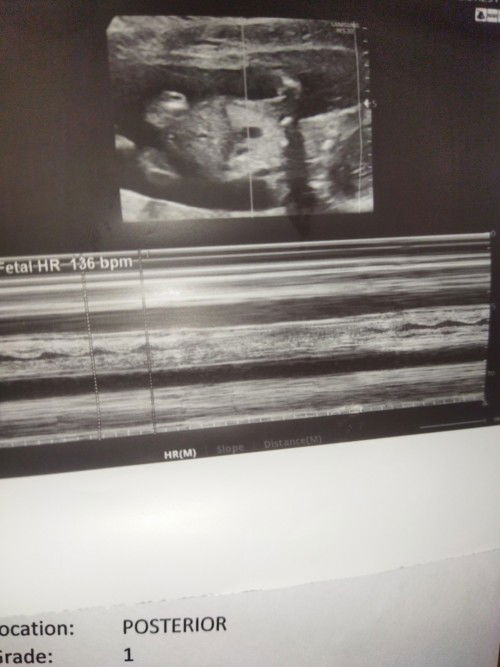

Sa tingin nyo po mga mommy, boy po or girl??#1stimemom #advicepls